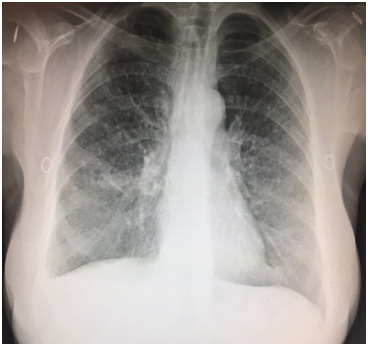

A 57 year old Caucasian female was admitted for dry cough, fever, loss of appetite and chest pain for three weeks. She had a history of tonsillectomy, ankylozing spondylitis, uveitis, pelvis fracture and tibia fracture. Her father died of colonic carcinoma. Her mother had hypertension and previous pulmonary tuberculosis. The patient was under treatment with certolizumab, methotrexate, and prednisolonefor ankylozing spondylitis and uveitis. Daily 300mg isoniazid was also given simultaneously with certolizumab for prophylaxis. Initial laboratory findings revealed WBC 8.2X103/mm3, hemoglobin 10.8g/dl, platelets 341X103mm3, lymphocytes 1.4X103/mm3, creatinine 0.74mg/dl, AST 18IU/L, ALT 18IU/Lmm3, LDH 167IU/L, albumine 3.56gr/dl, CRP 18.6 mg/dl, and calcium 9.1 mg/dl. ECG showed sinus ryhtm. Tuberculin test was negative. Chest x-rayshowed diffuse miliary nodules, alveolar infiltration in the right lower lobe, and right pleural effusion (Figure 1). Pleural protein 4.57g/dl, LDH 353U/L, and albumin 3.56g/dl. Pleural fluid had 1540cells/mm3 with a 74% lymphocyte ratio. Pleural fluid ADA was 114U/L (normal 0-40 U/L). The pleural fluid was exudative compatible with tuberculosis. Computed tomography of the thorax revealed diffuse miliary nodules, infiltration in the right anterior segment of the lower lobe, and right pleural effusion (Figures 2-4). Sputum stains was positive for acid-fast bacilli. Mycobacterium tuberculosis was isolated from the sputum culture. The final diagnosis was miliary tuberculosis associated with certolizumab occuring on the third month of treatment. The patient was commenced on pyrazinamide, isoniazid, rifampicine, and ethambutol treatment for tuberculosis while certolizumab treatment was stopped.

Figure 4 Axial computed tomography showing diffuse miliary nodules and right pleural effusion at the carenal level.